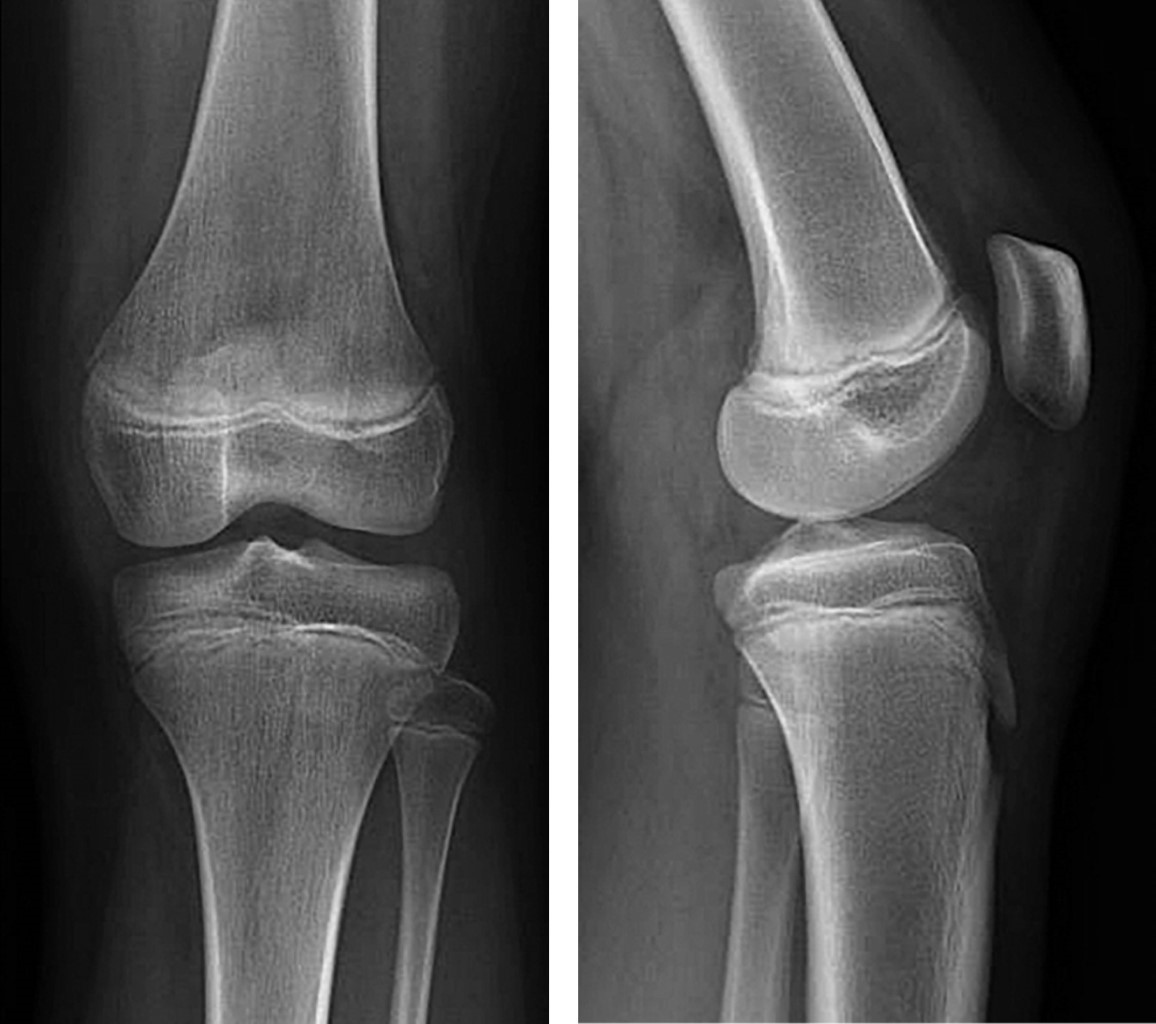

A 12-year-old female gymnast presented with acute pain on the back of her left knee sustained during training. Initial radiographs were unremarkable (Figure 1), prompting further imaging for a definitive diagnosis. A computed tomography (CT-scan) revealed the bone component of the lesion and the degree of displacement (Figure 2). Magnetic resonance imaging demonstrated an avulsion fracture at the posteromedial aspect of the femur arising from the origin of the tendon of the medial gastrocnemius muscle (Figure 3). There were no associated injuries or tears to the medial head of the gastrocnemius muscle.

Figure 1